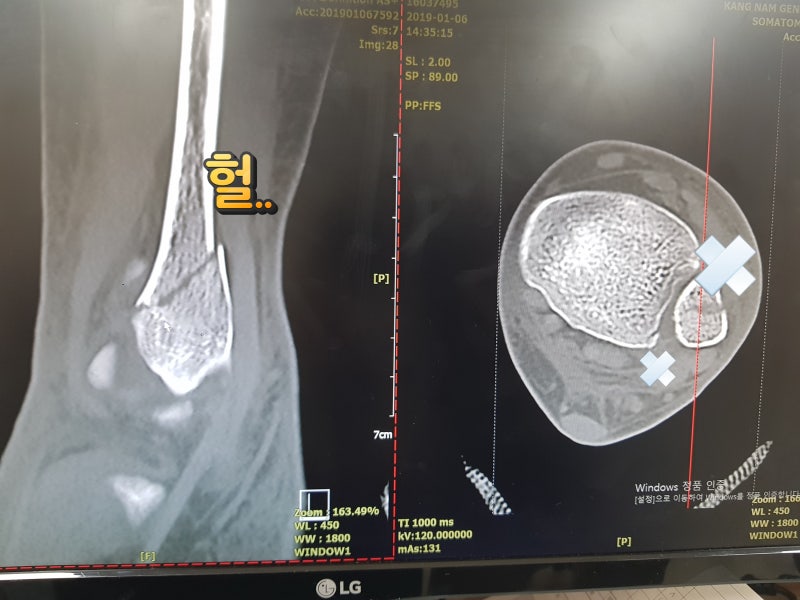

· 다리의 부종이 줄어 발등의 핏줄도 보이고 뼈??도보면